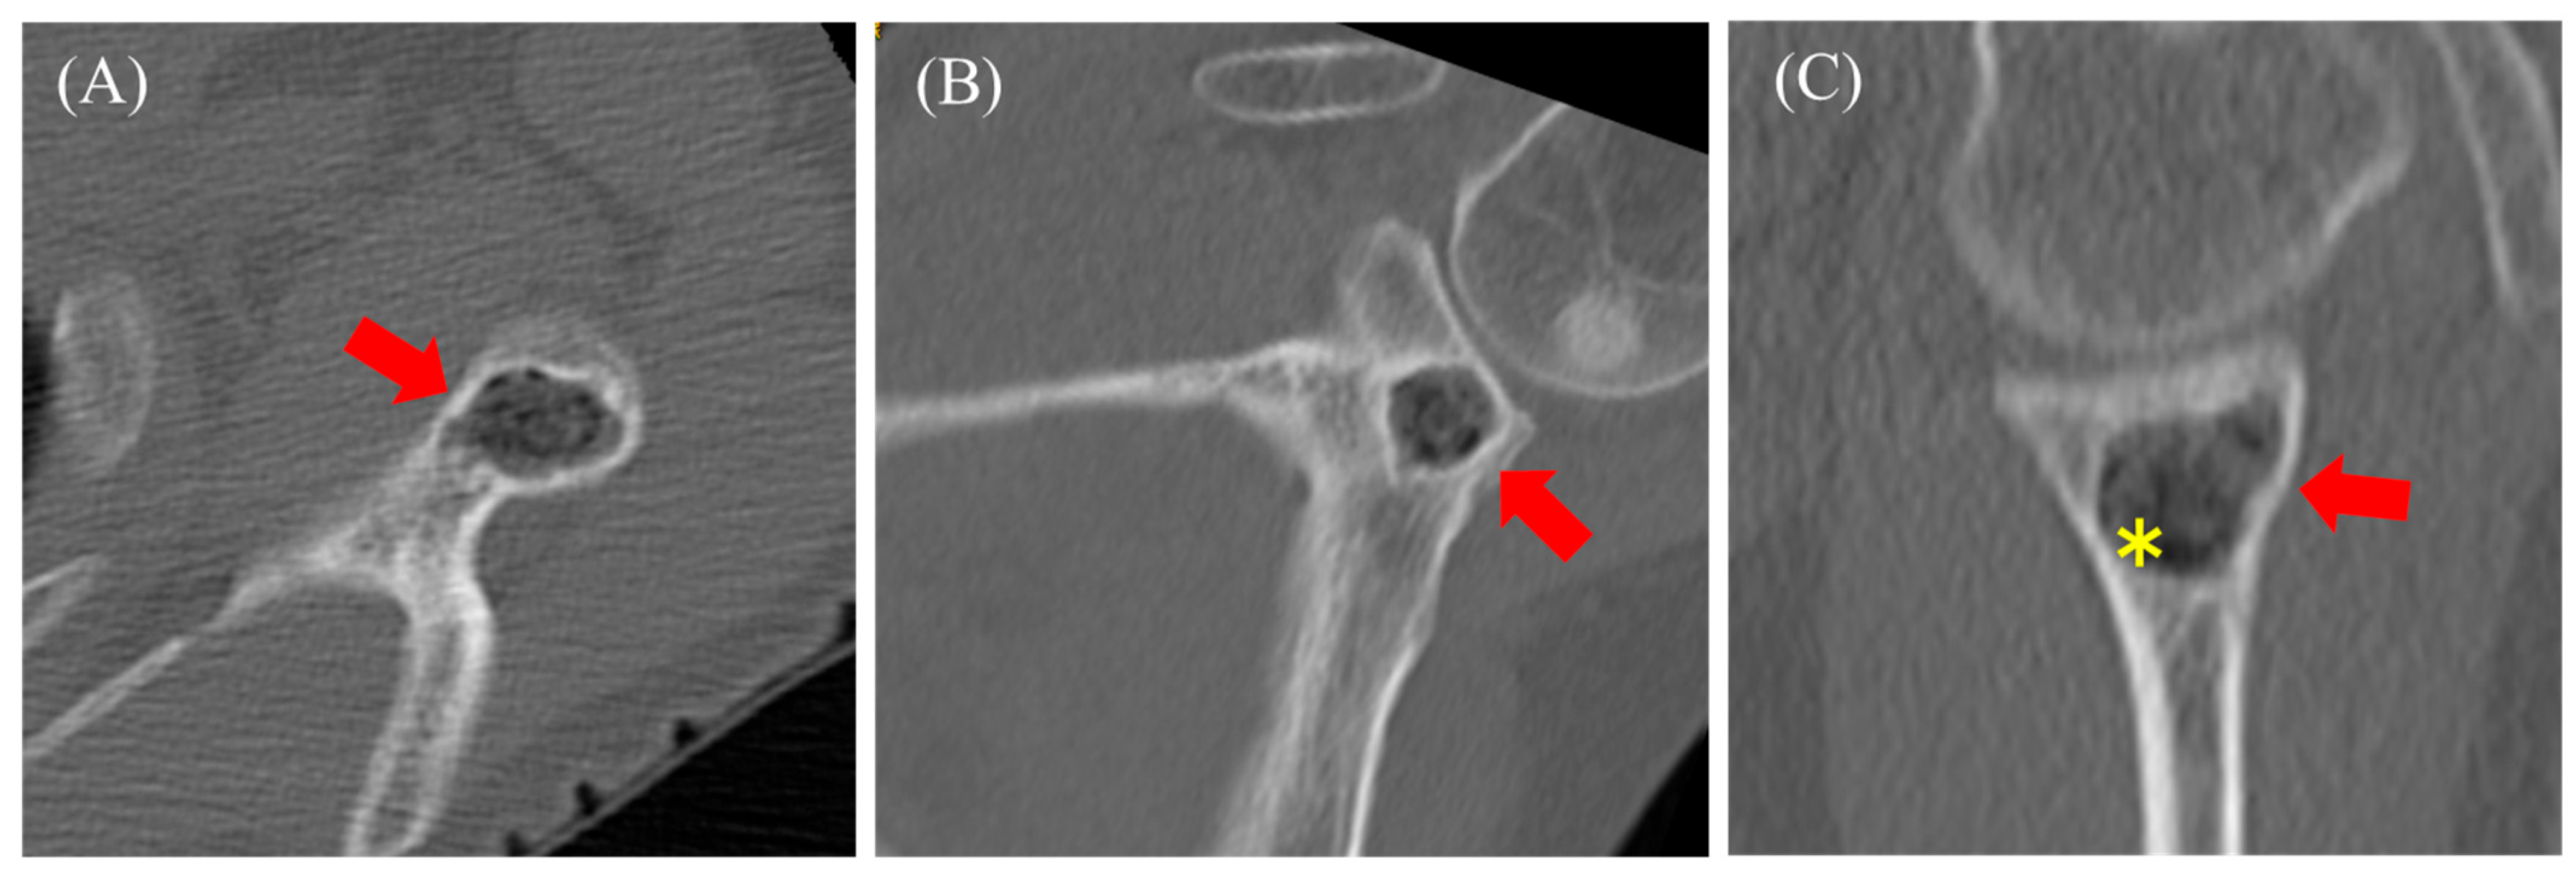

2.1. Case 1